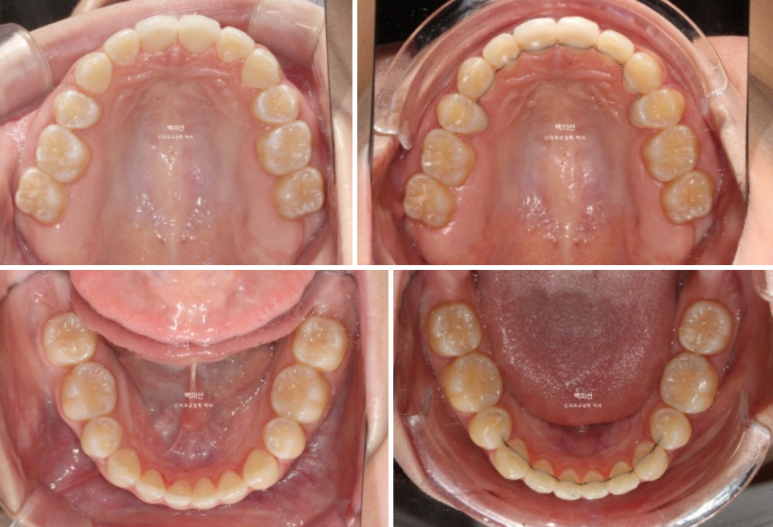

25.02~25.06

어금니교합 뿐만 아니라 앞니 교합까지 더 긴밀해졌습니다.

뼈속에서 붙어있던 송곳니와 작은어금니 뿌리들은 4개월의 교정으로 비로소 서로 멀어지며 정렬을 찾았습니다.